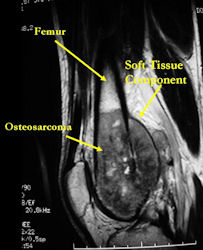

MRI: Osteosarcoma of distal femur with skip metastasis to proximal femur

MRI with contrast (gadolinium) of the extremity Best for:

- determining intraosseous extent (size) of the tumor and size of the soft tissue component

- determining relationship of tumor to neurovascular structures

- detecting skip metastases

- Most conventional osteosarcomas (90-95%) extend through the bone into the soft tissues and form a soft tissue mass outside of the bone